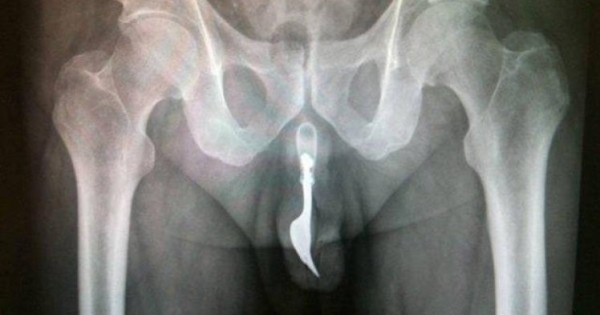

为了纾解性慾,人们创造了很多情趣用品,但还是有不少人甘愿冒险,使用那些特别的工具自慰。不久前,一名50岁的宏都拉斯男子就因为下体被卡住去医院求助。他将GG放进瓶子口,却再也拿…

越来越多人使用情趣用品,虽然它们能够给人带来纯粹的快乐,但如果使用不当,也很容易发生危险。下面这些人就富有超乎常人的冒险精神,为了追求身体的快乐,他们做了很多不可思议的事…